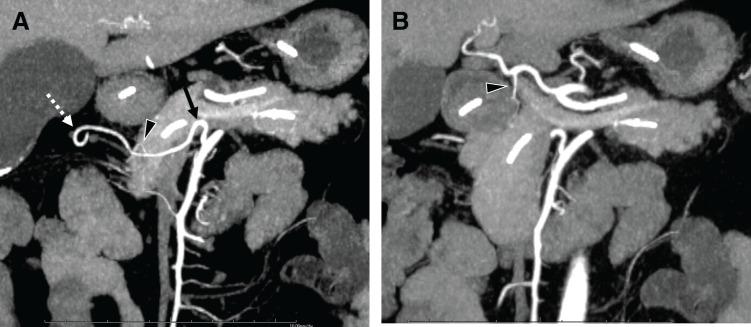

A 63-year-old woman presented with recurrent pancreatitis due to a cystic lesion in the pancreatic body. Imaging suggested a branch-duct intraductal papillary mucinous neoplasm with substantial ductal stenosis. Multidetector CT (MDCT) revealed a rare anatomical variant: the GDA, arising from the SMA and traversing along the inferior border of the pancreas. Laparoscopic distal pancreatectomy was performed after placing an endoscopic nasopancreatic drainage tube. The aberrant GDA was successfully preserved through careful dissection and vessel loop isolation. Pancreatic transection was completed without vascular injury. A postoperative pancreatic fistula developed and was conservatively managed. Histopathological examination confirmed that the lesion was an intraductal papillary mucinous carcinoma without any invasive features. Follow-up MDCT revealed sustained patency and perfusion of the preserved GDA, right gastroepiploic artery, and anterior superior pancreaticoduodenal artery.

一名63岁女性因胰体部囊性病变出现复发性胰腺炎。影像学检查提示为分支导管内乳头状黏液性肿瘤,伴有明显的导管狭窄。多排螺旋CT(MDCT)显示一种罕见的解剖变异:GDA起源于SMA,并沿胰腺下缘走行。在内镜下鼻胰引流管置入后,进行了腹腔镜远端胰腺切除术。通过仔细解剖和血管环分离,成功保留了异常的GDA。胰腺横断术在无血管损伤的情况下完成。术后发生了胰瘘,并进行了保守治疗。组织病理学检查证实病变为导管内乳头状黏液癌,无任何浸润性特征。随访MDCT显示保留的GDA、胃网膜右动脉和胰十二指肠上前动脉持续通畅且有灌注。